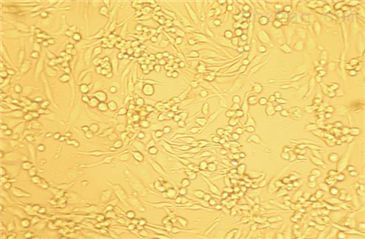

5)细胞生长方式:上皮样,多角形细胞,贴壁培养。

兔原代肺微血管内皮细胞

细胞详述:

肺微血管内皮细胞构成半选择性屏障,该屏障对于肺气体交换,调节液体和可溶物在血液与肺间质之间的流动具有重要意义。它还具有代谢功能,可以执行一定的非呼吸功能。在肺损伤中,肺微血管内皮细胞是活性氧类的重要靶细胞之一。在肺炎的发生过程中,神经体液介质和氧化剂作用于内皮细胞,使得细胞间隙渗透性增加,蛋白质由血液进入间质。细胞间隙渗透性的增加导致低氧血症,出现成人呼吸窘迫综合征和非心源性肺水肿。